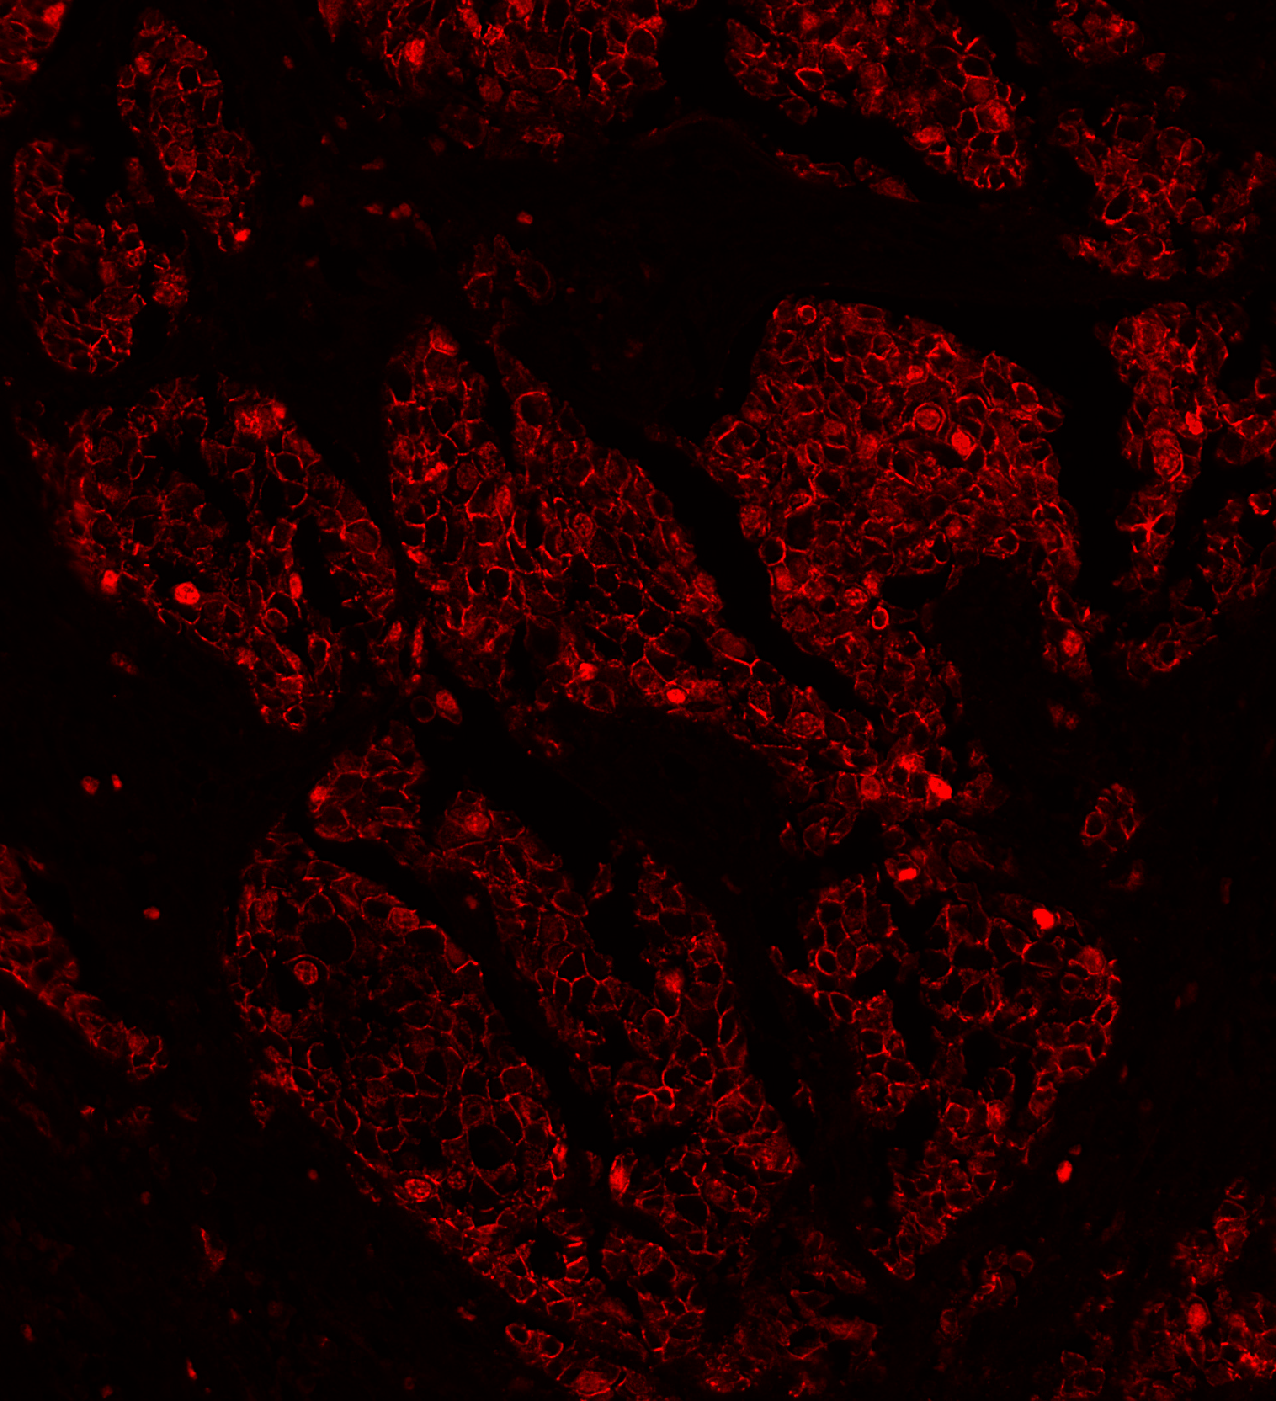

Sarpeda Plex — Marker Separation

Breast tissue: E-cadherin and Ki-67 labeled with the same fluorophore, then separated by AI. Green nuclei (Ki-67) clearly emerge from the red membrane staining (E-cadherin).

Breast Plex output

Breast input

Input Plex Output

Breast training image

Training image — markers imaged in separate conventional channels